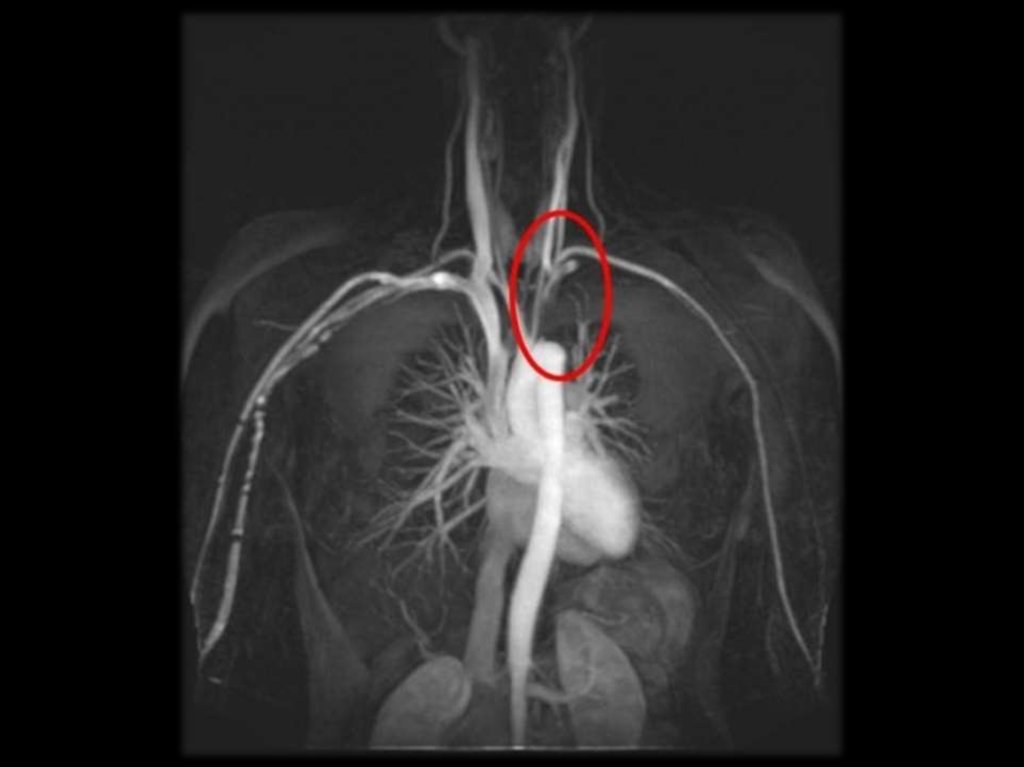

52. БОЛЕЗНЬ ТАКАЯСУ (неспецифический аортоартерии)

53. Определение

Васкулит,

характеризующийся

воспалительными

и

деструктивными

изменениями в стенке дуги аорты и её

основных ветвей.

В США распространённость составляет 2,6

на

1

млн.

населения.

Встречается

преимущественно у молодых женщин,

средний возраст составляет 10 – 30 лет.

54. Диагностические критерии (АКР, 1990)

1. Возраст при появлении первых симптомов

болезни < 40 лет.

2. Перемежающаяся хромота в конечностях.

3. Ослабление пульсации на плечевых артериях.

4. Стойкая разница САД на руках > 10 мм.

5. Сужение подключичной артерии или аорты,

проявляющийся шумом.

6. Изменения при ангиографии: сужение или

окклюзия самой аорты, её основных стволов или

крупных артерий в проксимальной части на

верхних или нижних конечностях не связанные с

атеросклерозом.

Изменения

обычно

носят

сегментарный или очаговый характер.

Диагноз достоверен

признаков.

при

наличии

более

трёх

Классификация болезни Такаясу по уровню поражения аорты